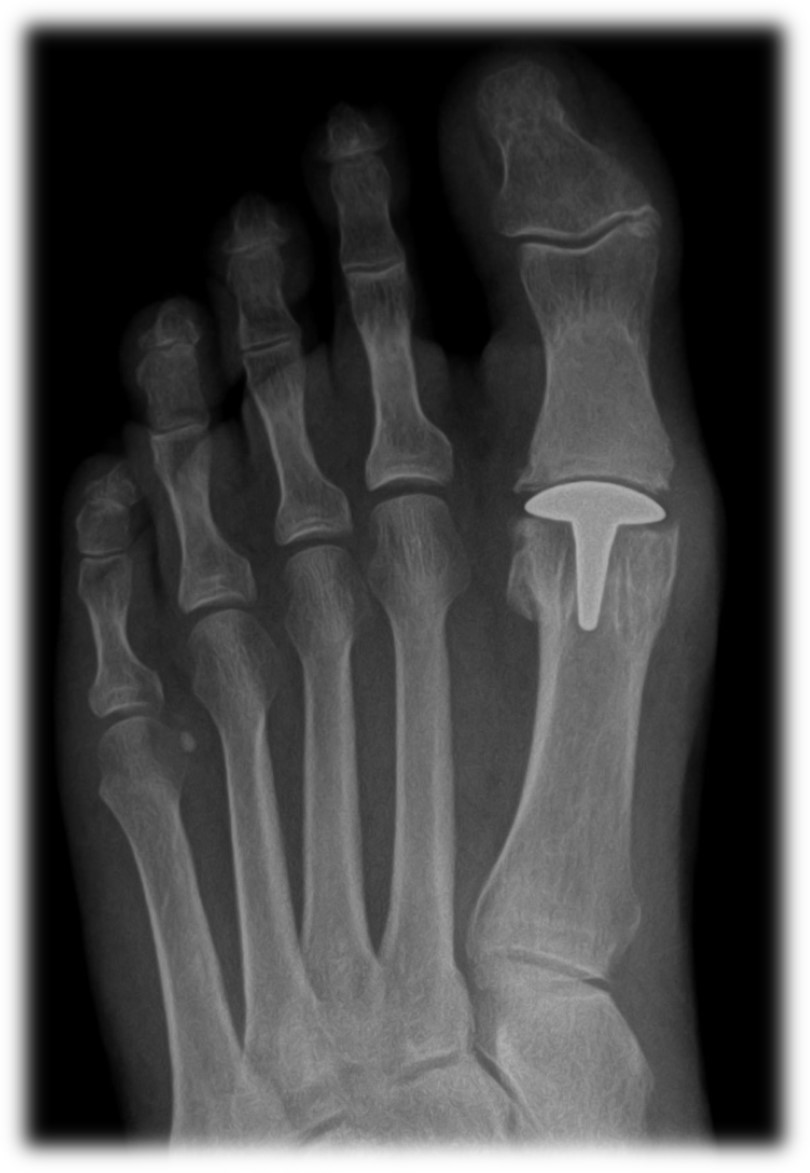

From medapparatus.com

Medical Apparatus Imaging Guide joint arthroplasty Toe Joint Replacement Cost Uk the toemotion® is a specifically contoured metal replacement which resurfaces the degenerate joint by replacing both the 'ball & socket' joints of. mr gordon uses the cartiva big toe joint replacement as it gives good results, has a quick recovery time after surgery and has. unresolved big toe stiffness or a severely damaged joint may need toe. Toe Joint Replacement Cost Uk.